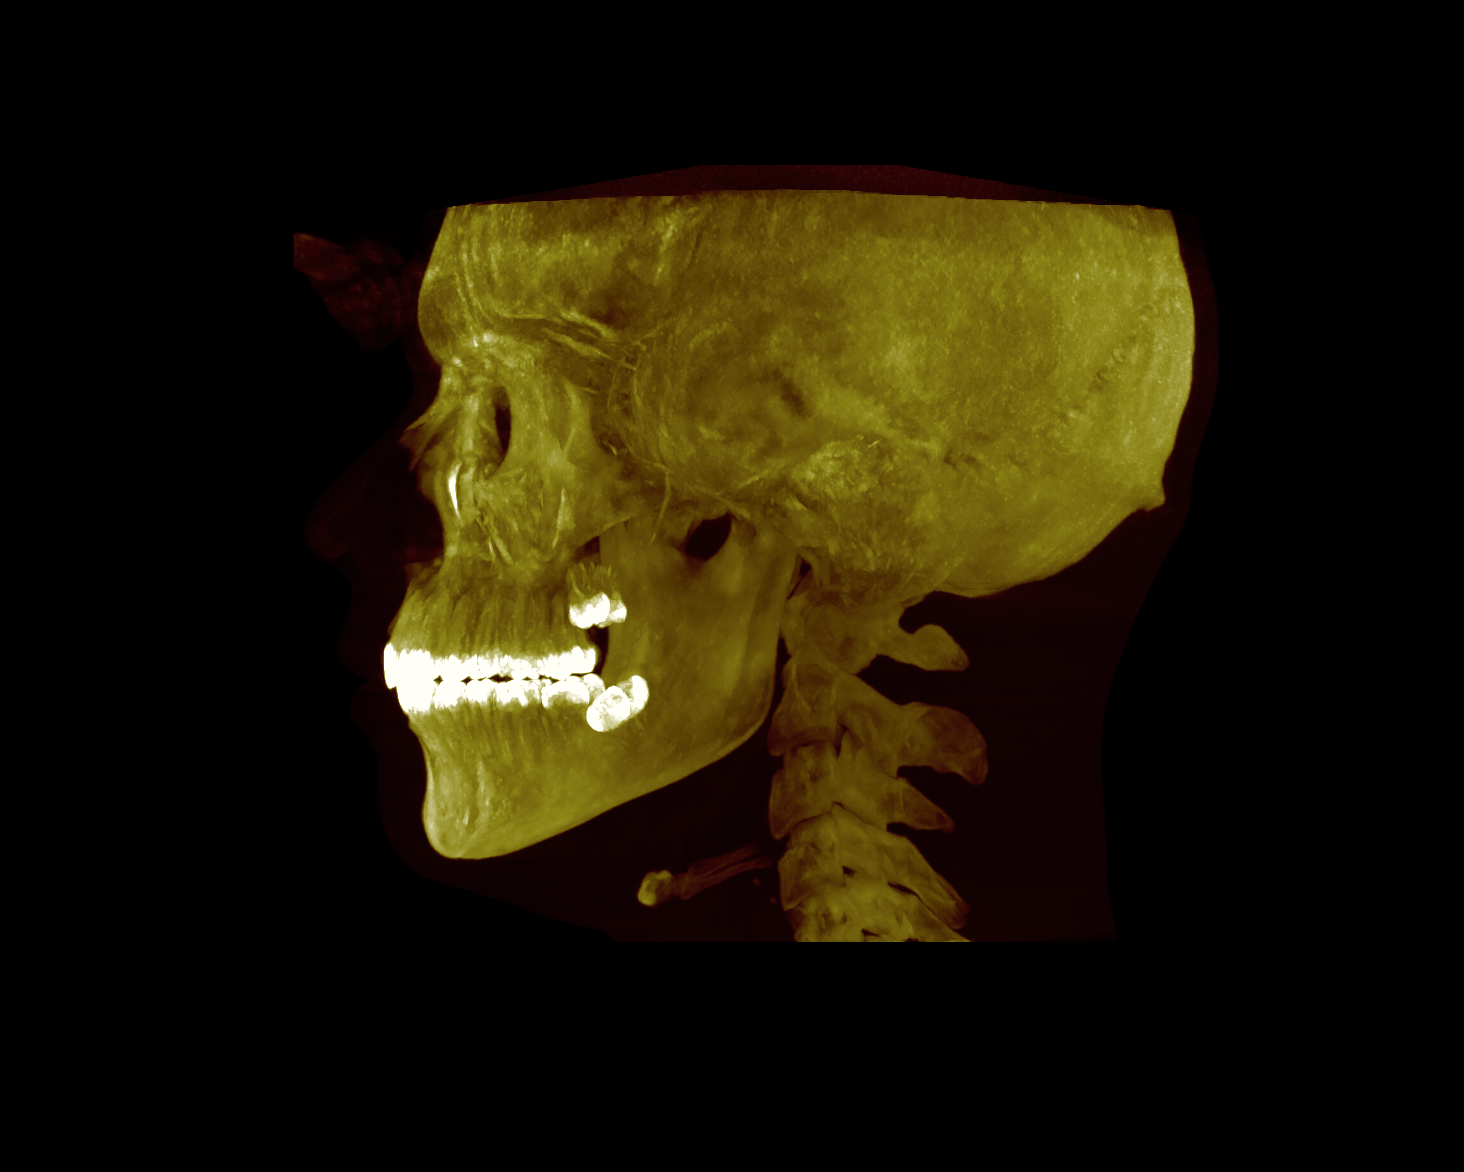

I currently have braces and it lowk fucked my maxilla by bringing it back, so hopefully the lefort 1 fixes it, and bsso to move my lower jaw.

During the planning i will tell pera that i want a downgraft to the maxilla alongside forward movement. Because i have a short face i bite down

I currently have braces and it lowk fucked my maxilla by bringing it back, so hopefully the lefort 1 fixes it, and bsso to move my lower jaw.

During the planning i will tell pera that i want a downgraft to the maxilla alongside forward movement. Because i have a short face i bite down